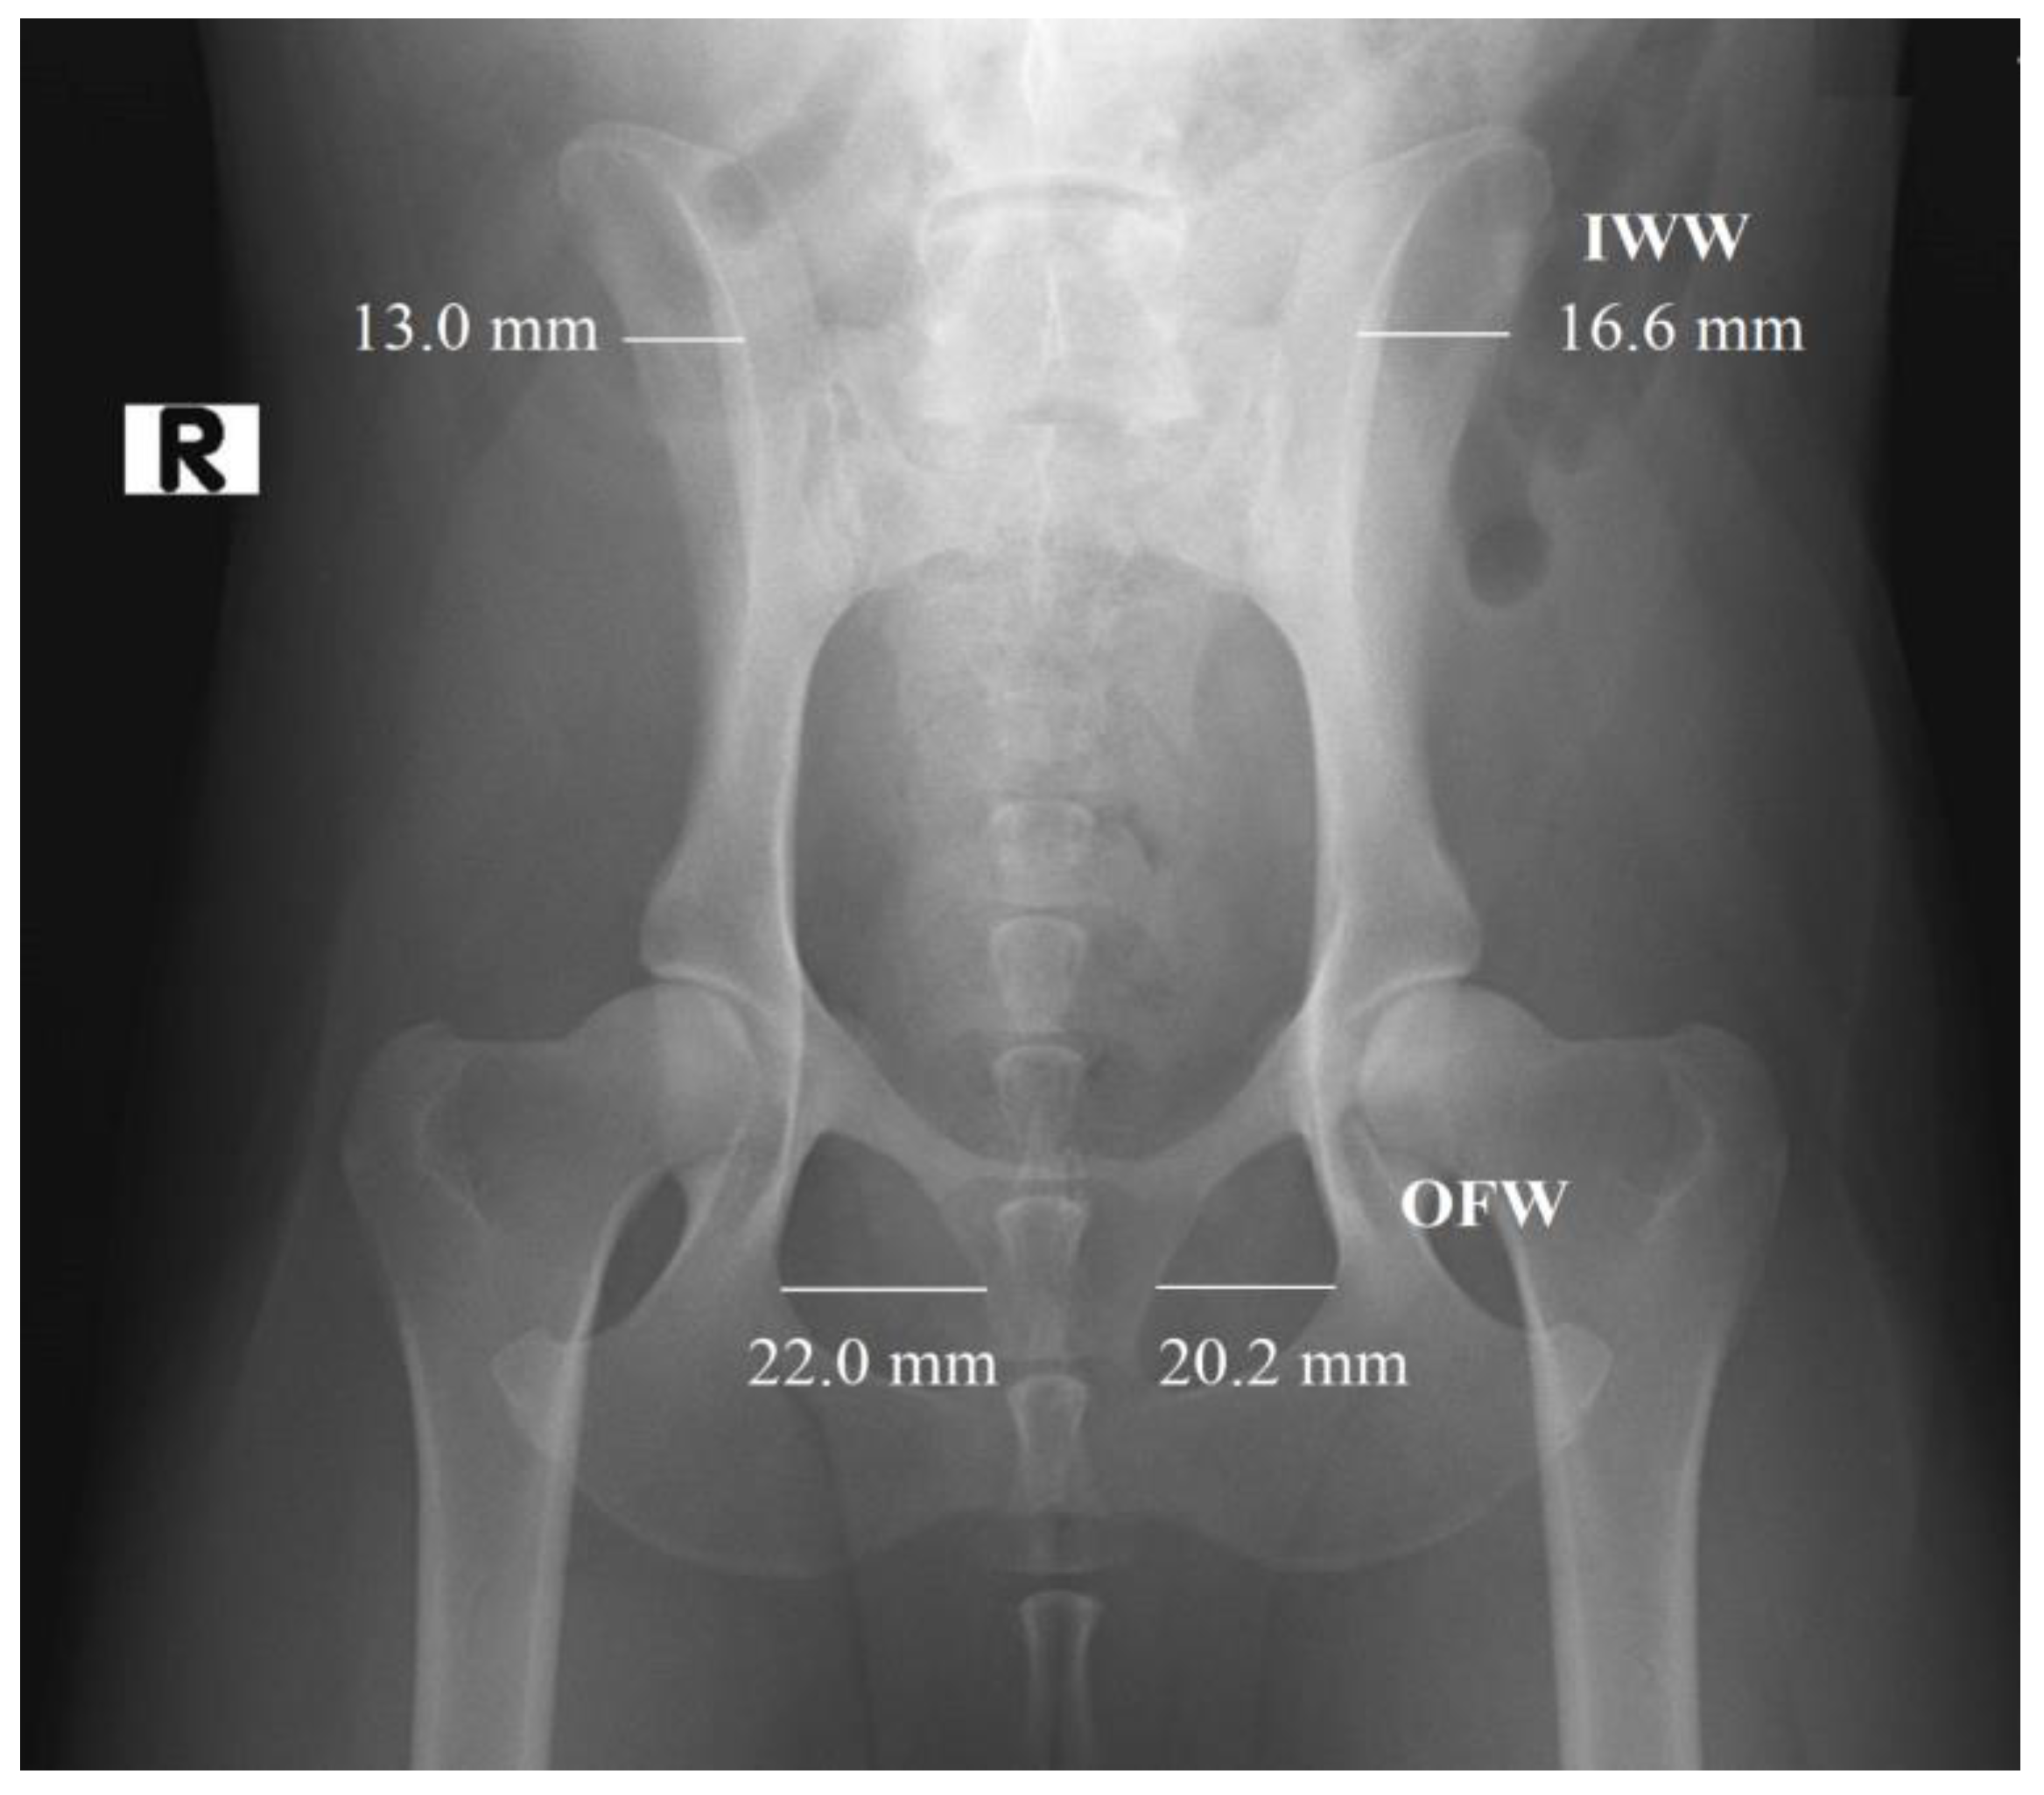

In the first part of the study, 203 radiographs in DICOM format were manually annotated using the polygonal image annotation tool, LabelMe [20], to delineate the right and left obturator foramina. The AIWW was calculated by measuring the widths of the right and left iliac wings in millimeters. A horizontal line was drawn between the dorsal and ventral iliac cortices at the cranial aspect of the sacroiliac joint on both sides (Figure 1). The AIWW was determined by subtracting the width of the right wing from that of the left [10]. The AOFW was calculated by measuring the widths of the right and left obturator foramina in millimeters. A horizontal line was drawn between the medial and lateral aspects of each foramen at its widest points (Figure 1). The AOFW was determined by subtracting the width of the right obturator foramen from that of the left [10]. The AIWW and AOFW, measured in millimeters (x), were used separately to estimate the degrees of pelvic rotation (y) through the following regression equations: y = 0.997x + 0.061 for AIWW and y = 1.644x − 0.912 for AOFW [10]. The AOFA was calculated by measuring the areas of the right and left obturator foramina in square millimeters. For this purpose, the areas were outlined using semantic segmentation, employing pixel-wise labeling to trace the boundaries of both obturator foramina (Figure 2). The AOFA was determined by subtracting the area of the right obturator foramen from that of the left.

Figure 2. Delimitation of the obturator foramina using the LabelMe annotation tool for the calculation of the asymmetry in obturator foramina areas (AOFAs) in ventrodorsal hip extended (VDHE) view. The obturator foramina areas are delimitated by greens points.